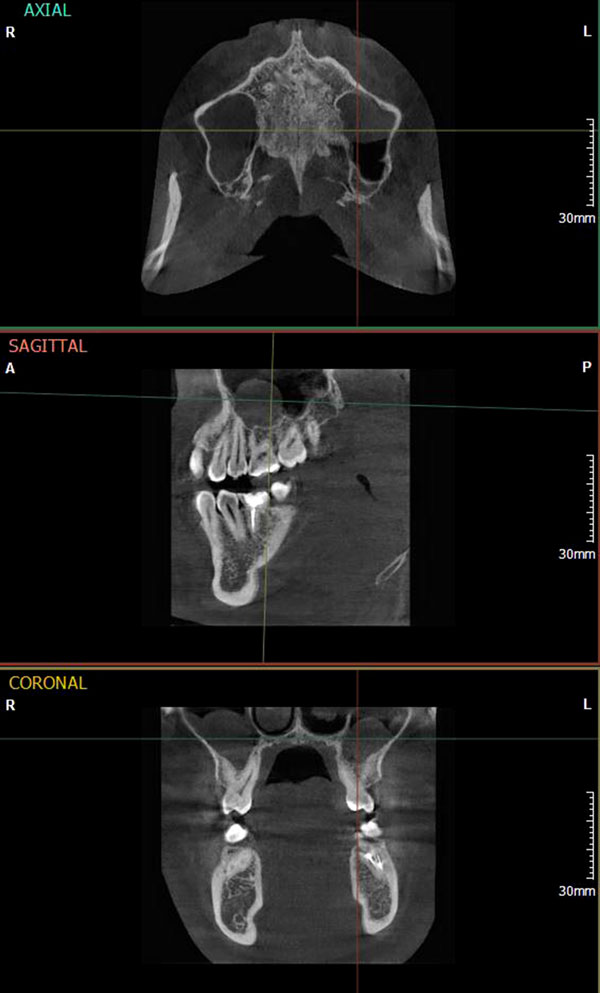

Полученные данные сравнительного изучения лучевых методов исследования показали, что ортопантомография оказалась недостаточно эффективной методикой как для уверенной диагностики перфорации стенки пазухи, так и для оценки сопутствующих воспалительных изменений. Результаты дентальной объемной томографии следует считать предпочтительнее, так как при исследовании отсутствовали артефакты от металла, не требовалась дополнительная постпроцессорная обработка и хорошо визуализировались сопутствующие воспалительные изменения в верхнечелюстной пазухе (Рис.1).

Рис. 1 Дентальная объемная томограмма – гипертрофия слизистой верхнечелюстных пазух с признаками сопутствующего воспалительного процесса.